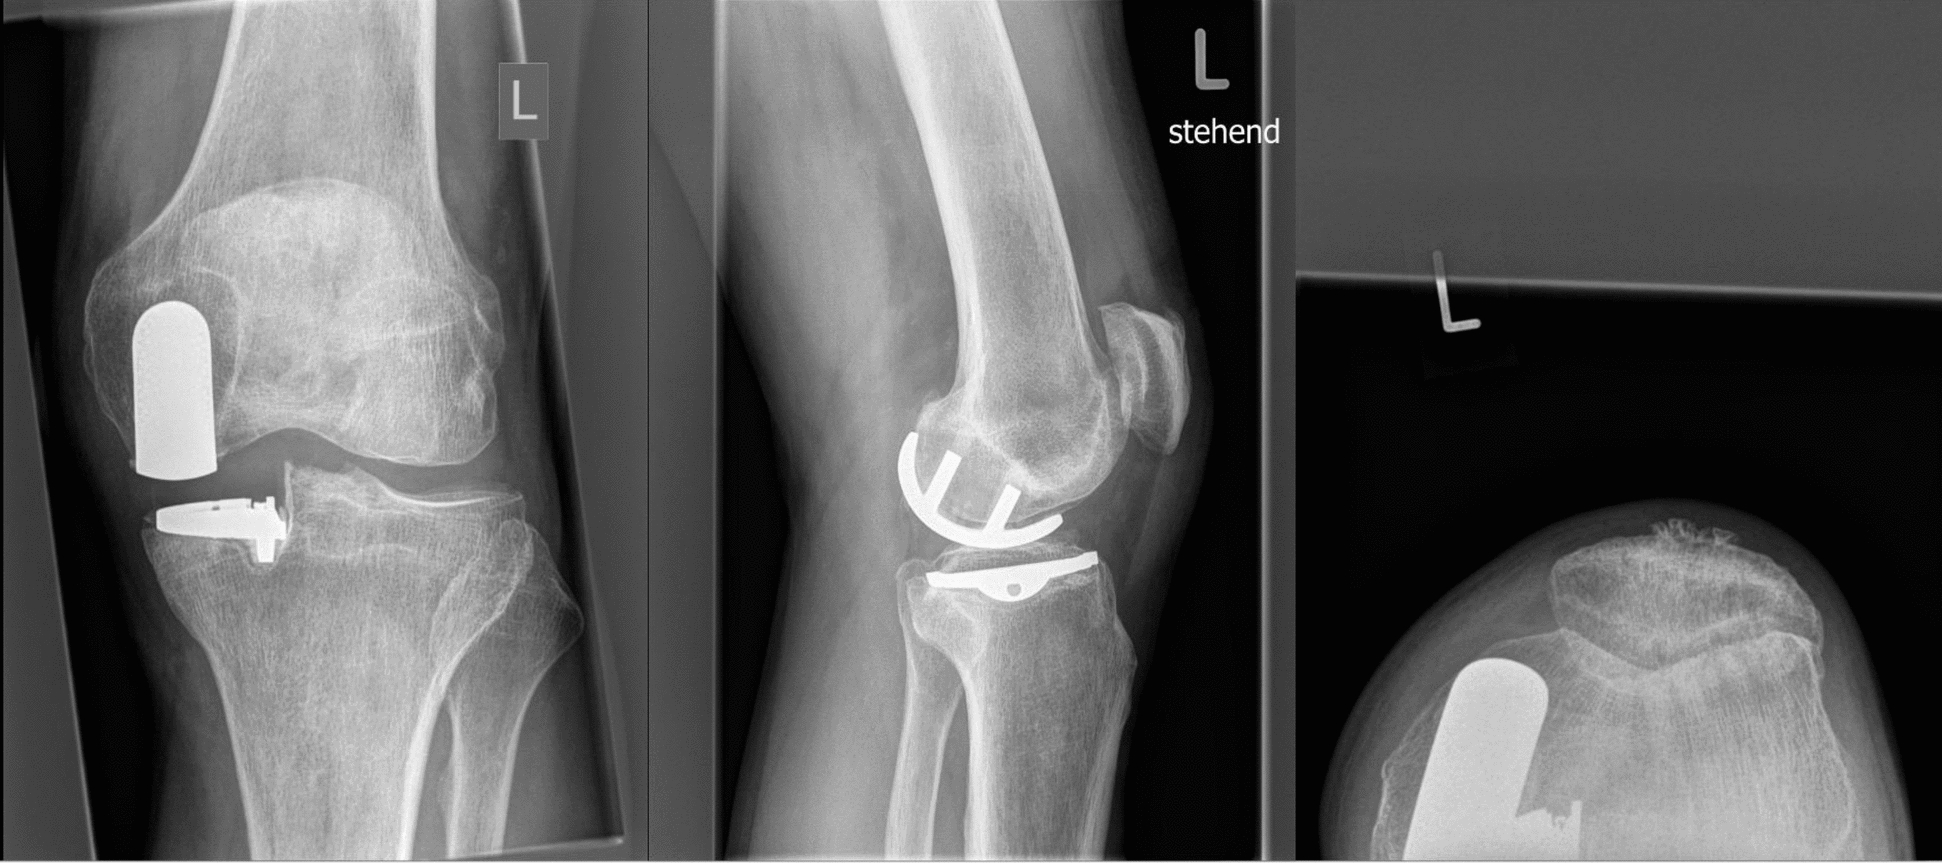

Methods: Imaging of patients who underwent revision surgery of a medial UKA to TKA for aseptic loosening of the tibial or femoral component was retrieved. Lower limb axes were evaluated using anteroposterior plain radiographs of the leg using the software MediCAD Knie 2D (mediCAD Hectec GmbH, Altdorf, Germany). The radiographic axes of revised patients were compared with established reference values, as defined by the MediCAD Knie 2D software and published literature, to identify common alignment patterns potentially associated with aseptic loosening.

Results: Data from 62 patients were analysed. Before the revision surgery, the joint line convergence angle (JLCA, P = 0.002) and the anatomical-mechanical angle (AMA, P < 0.0001) were statistically significantly greater than the corresponding reference values. In contrast, the mechanical lateral distal femoral angle (mLDFA, P < 0.0001), the mechanical and anatomical medial proximal tibial angle (mMPTA and aMPTA, P < 0.0001), and the mechanical and anatomical lateral distal tibial angle (mLDTA and aLDTA, P < 0.0001) were significantly lower than reference. No statistically significant difference was found in the mechanical lateral proximal femoral angle (mLPFA, P = 0.9) or in the mechanical axis deviation (MAD, P = 0.5) when compared to normative data.

Conclusion: Our cohort of patients revised from medial UKA to TKA for aseptic loosening frequently exhibited consistent deviations in lower limb alignment, particularly increased AMA and JLCA, and reduced mLDFA, mMPTA, and mLDTA. These subtle but recurrent patterns may alter load distribution across the medial compartment, contributing to implant micromotion and loosening. A detailed preoperative axis assessment may help identify patients at a higher biomechanical risk.